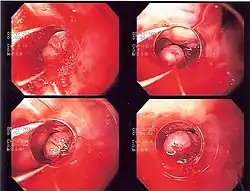

Endoscopic image of esophageal varices being ligated with rubber bands. The varix being ligated has a longitudinal red mark on it, termed the wale mark

A wale mark, red wale sign or wale sign is an endoscopic sign suggestive of recent hemorrhage, or propensity to bleed, seen in individuals with esophageal varices at the time of endoscopy. The mark has the appearance of a longitudinal red streak located on an esophageal varix. It derives its name from the visual similarity to patterns seen in the textile corduroy.[1]